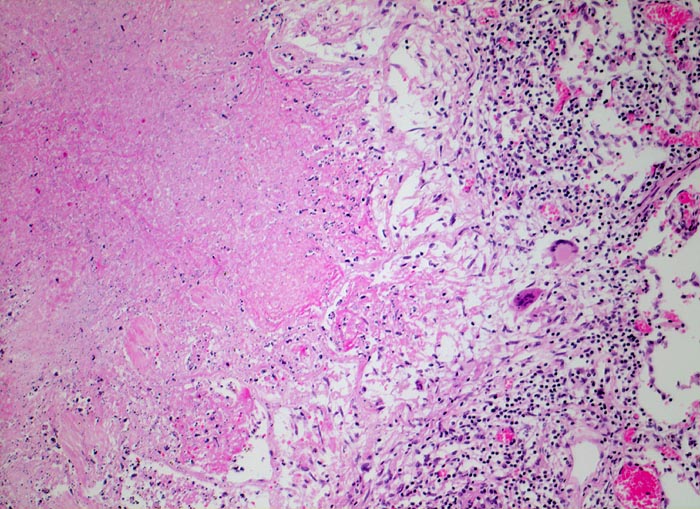

Lungentuberkulose: verkäsendes Granulom

Granulom mit zentraler verkäsender Nekrose gefolgt von einem Epitheloidzellwall mit Riesenzellen vom Langhanstyp und einem äusseren Saum von Lymphozyten.

Autoptisch wird ein akuter Myokardinfarkt der Vorderwand diagnostiziert. In beiden Lungen fallen oberlappenbetonte knotige weisse, teils kleeblattartige Infiltrate auf und eine subapikal gelegene kleine Kaverne. Einzelne hiläre Lymphknoten der rechten Seite weisen Verkalkungen auf und bilden zusammen mit einem subpleural im Mittellappen gelegenen verkalkten Herd den abgeheilten Primärkomplex. In den käsigen Nekrosen können vereinzelte säurefeste Stäbchen nachgewiesen werden.

Patient mit insulinpflichtigem Diabetes mellitus. Hospitalisation zur Behandlung einer PAVK. Während der Hospitalisation verstirbt der Patient an den Folgen eines Myokardinfarkts. Aufgrund der Autopsiediagnose wird eine Umgebungsuntersuchung eingeleitet.